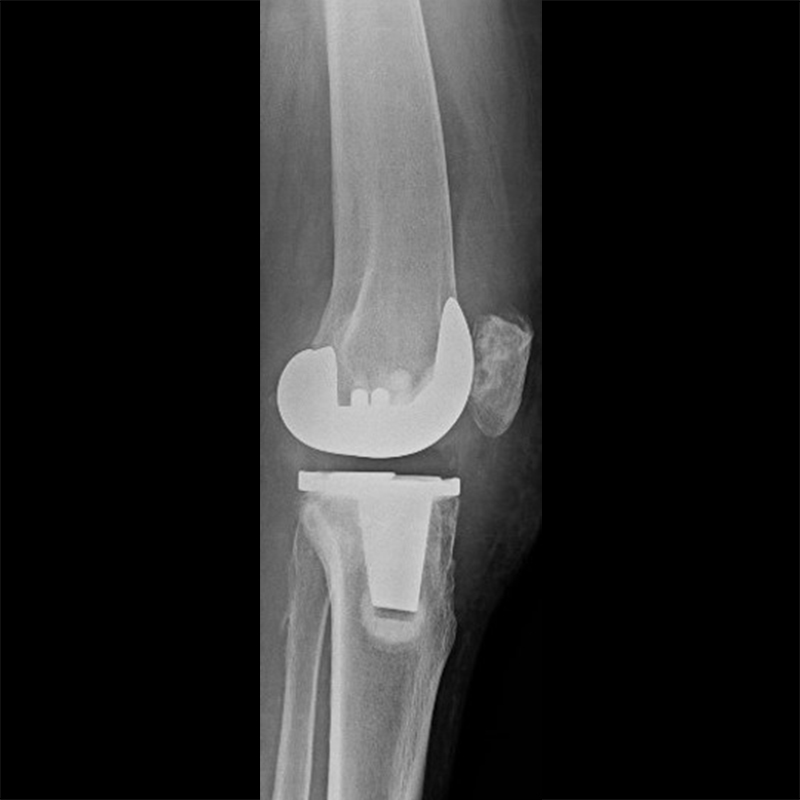

外院失敗本院再置換 首頁 案例分享 膝關節手術 外院失敗本院再置換 蕭女士 69歲 術前 術後 81歲 林女士 術前 術後 蕭女士 69歲 術前 術後 鄒女士 69歲 術前 術後 李女士 74歲 術前 術後 吳女士 71歲 術前 術後 謝女士 65歲 術前 術後